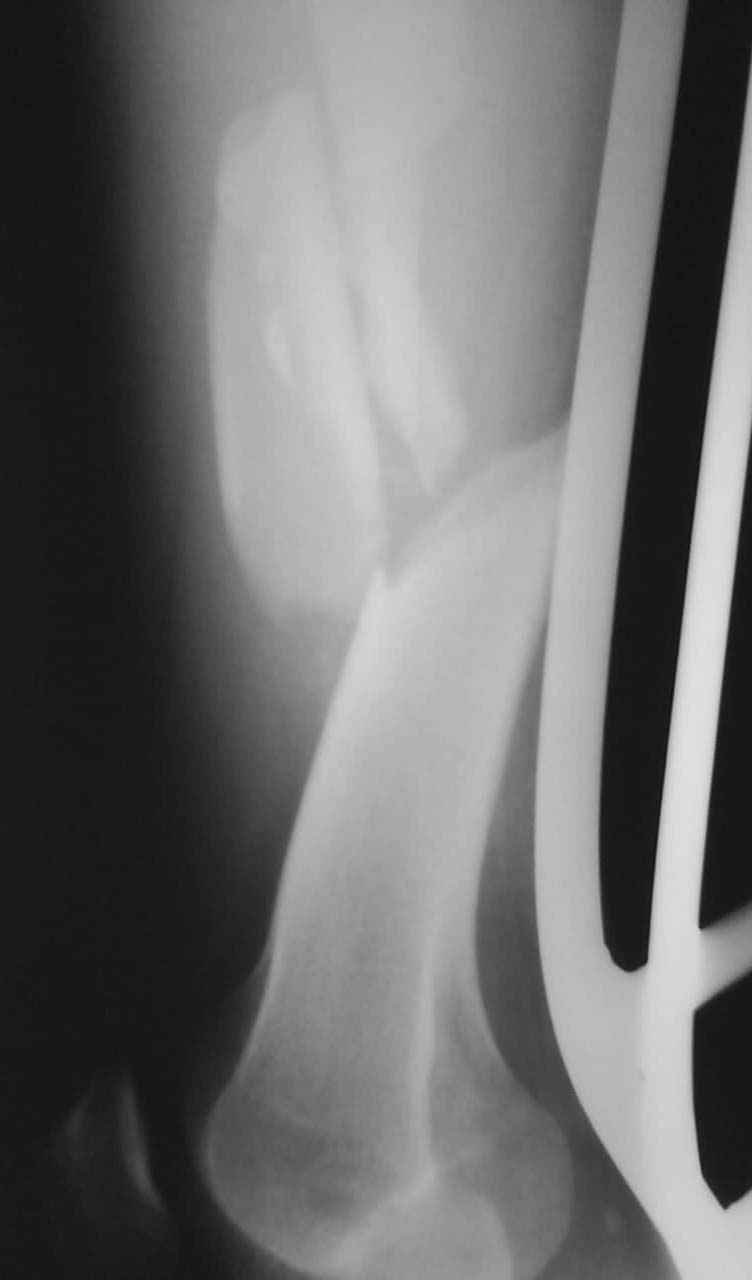

К нам поступил пациент 25 лет с закрытыми переломами обех бедренных

костей, прошел месяц после травмы. Слева-внутрисуставной перелом,

поэтому  выбор здесь очевиден, открытая репозиция, стабильная

фиксация, скорее всего LCP DF, а справа - мнения учёных, как

говорится, разошлись. Лично я, как лечащий врач, за закрытый

интрамедуллярный остеосинтез DFN. Со мной согласна половина

коллектива, другая - за интрамедуллярный остеосинтез (DFN,UFN) но с

открытой реопозицией, поскольку при закрытой методике все осколки

останутся где-то сбоку, получится дефект и вдруг не срастется!